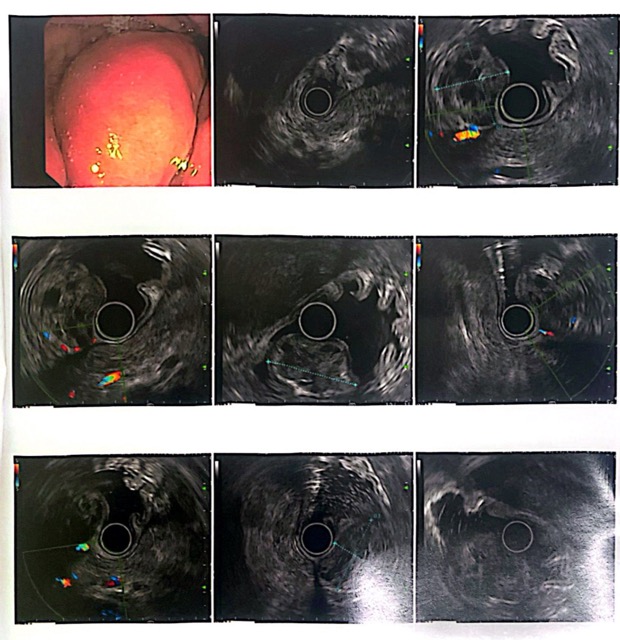

Because the patient was also old, the doctor chose endoscopic prostatectomy using Holmium Laser to completely remove the prostate tumor. The surgery was successfully performed by the surgical team of Hospital 199, led by resident doctor Do Van Hieu, with technical support from Dr. Chau Quy Thuan (Cho Ray Hospital). After surgery, the patient recovered well, had no heart rhythm disturbances, and could urinate easily and strongly. The patient felt more comfortable psychologically, had good aesthetics, and recovered quickly.

"Prostate enucleation with Holmium Laser is considered the most modern and effective method today. With this method, Laser energy is used to enucleate the prostate, push it into the bladder, combine with a tissue grinder to grind it and suck it out. The advantages of this method are safety, no incisions, less bleeding, shorter urinary circulation time and hospital stay" - Dr. Do Van Hieu added.